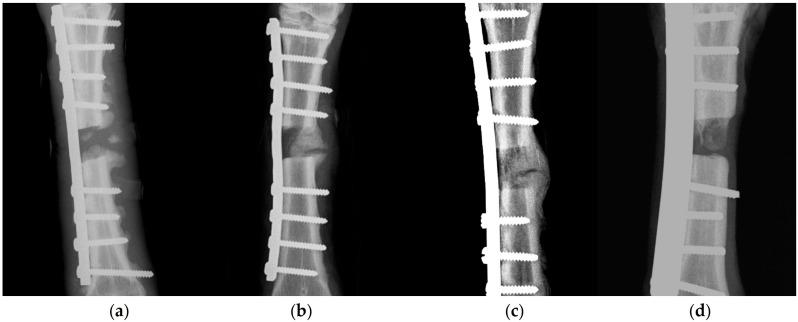

The objectives of the present study were to evaluate (a) the feasibility of using stromal vascular fraction (SVF) and nanocrystalline hydroxyapatite (nHA) paste in combination for the treatment of segmental bone defect, (b) the quality of the callus produced, (c) the potential improvement of the autograft technique, and (d) the direct comparison of the biomaterial to the use of autogenous cancellous bone. Unilateral, segmental mid-diaphyseal bone defect was created on the right metatarsus of skeletally mature sheep animals ( = 24) under anesthesia (D0). Residual segments were stabilized by stainless-steel plates and appropriate screws. Defects were managed as follows: group A: use of nHA paste to filling, group B: use of autogenous bone graft mixed with nHA bone paste, placed in defect, group C: use of SVF mixed with nHA bone paste injected into defect, group D: use of bone graft and SVF with nHA paste before apposition in bone defect. SVF had been previously isolated from adipose tissue of the animals intra-operatively after digestion with collagenase solution and neutralization. Animals were evaluated clinically and by X-raying and ultrasonographic examination of the defect, at regular intervals, until D90. Ultrasonographic assessment performed along the length of the defect included calculation of the length of the bone defect and assessment of vascularization. SVF was successfully isolated from group C and D animals, with the average yield being 1.77 × 10 cells. The comparison of clinical scores (based on the 'Kaler scale') on each post-operative day indicated significant differences between the four groups on D1 to D30 ( < 0.01); the median clinical score within group A was 2.5 for D1-D30 and 1 for the entire period; respective scores for other groups were 1.5 ( = 0.07) and 0 ( = 0.033). Differences in radiographic assessment scores were significant for scores obtained on D60 ( = 0.049) and D90 ( = 0.006). There was a significant difference between the four groups in the length of the bone defect, as assessed ultrasonographically, for the entire length of the study; median values were 8, 8.5, 6, and 8 mm for groups A, B, C, and D, respectively ( = 0.008). There was a significance in the differences between median scores obtained during the histopathological examination: 2, 11, 13.5, and 12 for group A, B, C, and D ( = 0.022). There was an inverse correlation between the overall scores of histopathological evaluations and the length of the bone defect (observed on D90) ( < 0.0001) and a correlation between the overall scores and the radiographic assessment scores (obtained on D90) ( < 0.0001). This is the first study in which the efficacy of fresh autologous Stromal Vascular Fraction (SVF) from adipose tissue in enhancing bone healing in a long, weight-bearing, diaphyseal bone was evaluated. It is concluded that the lumbosacral region was an attractive site for harvesting adipose tissue, the use of SVF contributed to faster rehabilitation post-operatively, and SVF significantly enhanced bone formation; in general, the results indicated an osteogenic potential of SVF comparable to the gold standard autologous bone graft.

(a)联合使用基质血管成分(SVF)和纳米晶羟基磷灰石(nHA)糊剂治疗节段性骨缺损的可行性;(b)所产生骨痂的质量;(c)自体移植技术的潜在改进;(d)将该生物材料与自体松质骨的使用进行直接比较。在麻醉下(D0),在骨骼成熟的绵羊动物(n = 24)的右跖骨上制造单侧、节段性骨干中部骨缺损。残余节段用不锈钢板和合适的螺钉固定。骨缺损的处理如下:A组:使用nHA糊剂填充;B组:使用自体骨移植混合nHA骨糊剂,置于缺损处;C组:使用SVF混合nHA骨糊剂注入缺损处;D组:在骨缺损对接前使用骨移植和含nHA糊剂的SVF。SVF先前已在术中用胶原酶溶液消化并中和后从动物的脂肪组织中分离出来。定期对动物进行临床评估,并对缺损部位进行X线和超声检查,直至D90。沿缺损长度进行的超声评估包括计算骨缺损的长度和评估血管化情况。在C组和D组动物中成功分离出SVF,平均产量为1.77×10⁶个细胞。术后每天的临床评分(基于“Kaler量表”)比较表明,在D1至D30期间,四组之间存在显著差异(P < 0.01);A组在D1 - D30的临床评分中位数为2.5,整个期间为1;其他组的相应评分为1.5(P = 0.07)和0(P = 0.033)。在D60(P = 0.049)和D90(P = 0.006)获得的放射学评估评分存在显著差异。在整个研究期间,通过超声评估,四组在骨缺损长度方面存在显著差异;A、B、C和D组的中位数分别为8、8.5、6和8 mm(P = 0.008)。组织病理学检查获得的中位数评分之间存在显著差异:A、B、C和D组分别为2、11、13.5和12(P = 0.022)。组织病理学评估的总体评分与骨缺损长度(在D90观察到)之间存在负相关(P < 0.0001),与放射学评估评分(在D90获得)之间存在相关性(P < 0.0001)。这是第一项评估来自脂肪组织的新鲜自体基质血管成分(SVF)在促进长的、负重的骨干骨愈合方面疗效的研究。得出的结论是,腰骶部是采集脂肪组织的理想部位,SVF的使用有助于术后更快康复,且SVF显著增强骨形成;总体而言,结果表明SVF的成骨潜力与金标准自体骨移植相当。